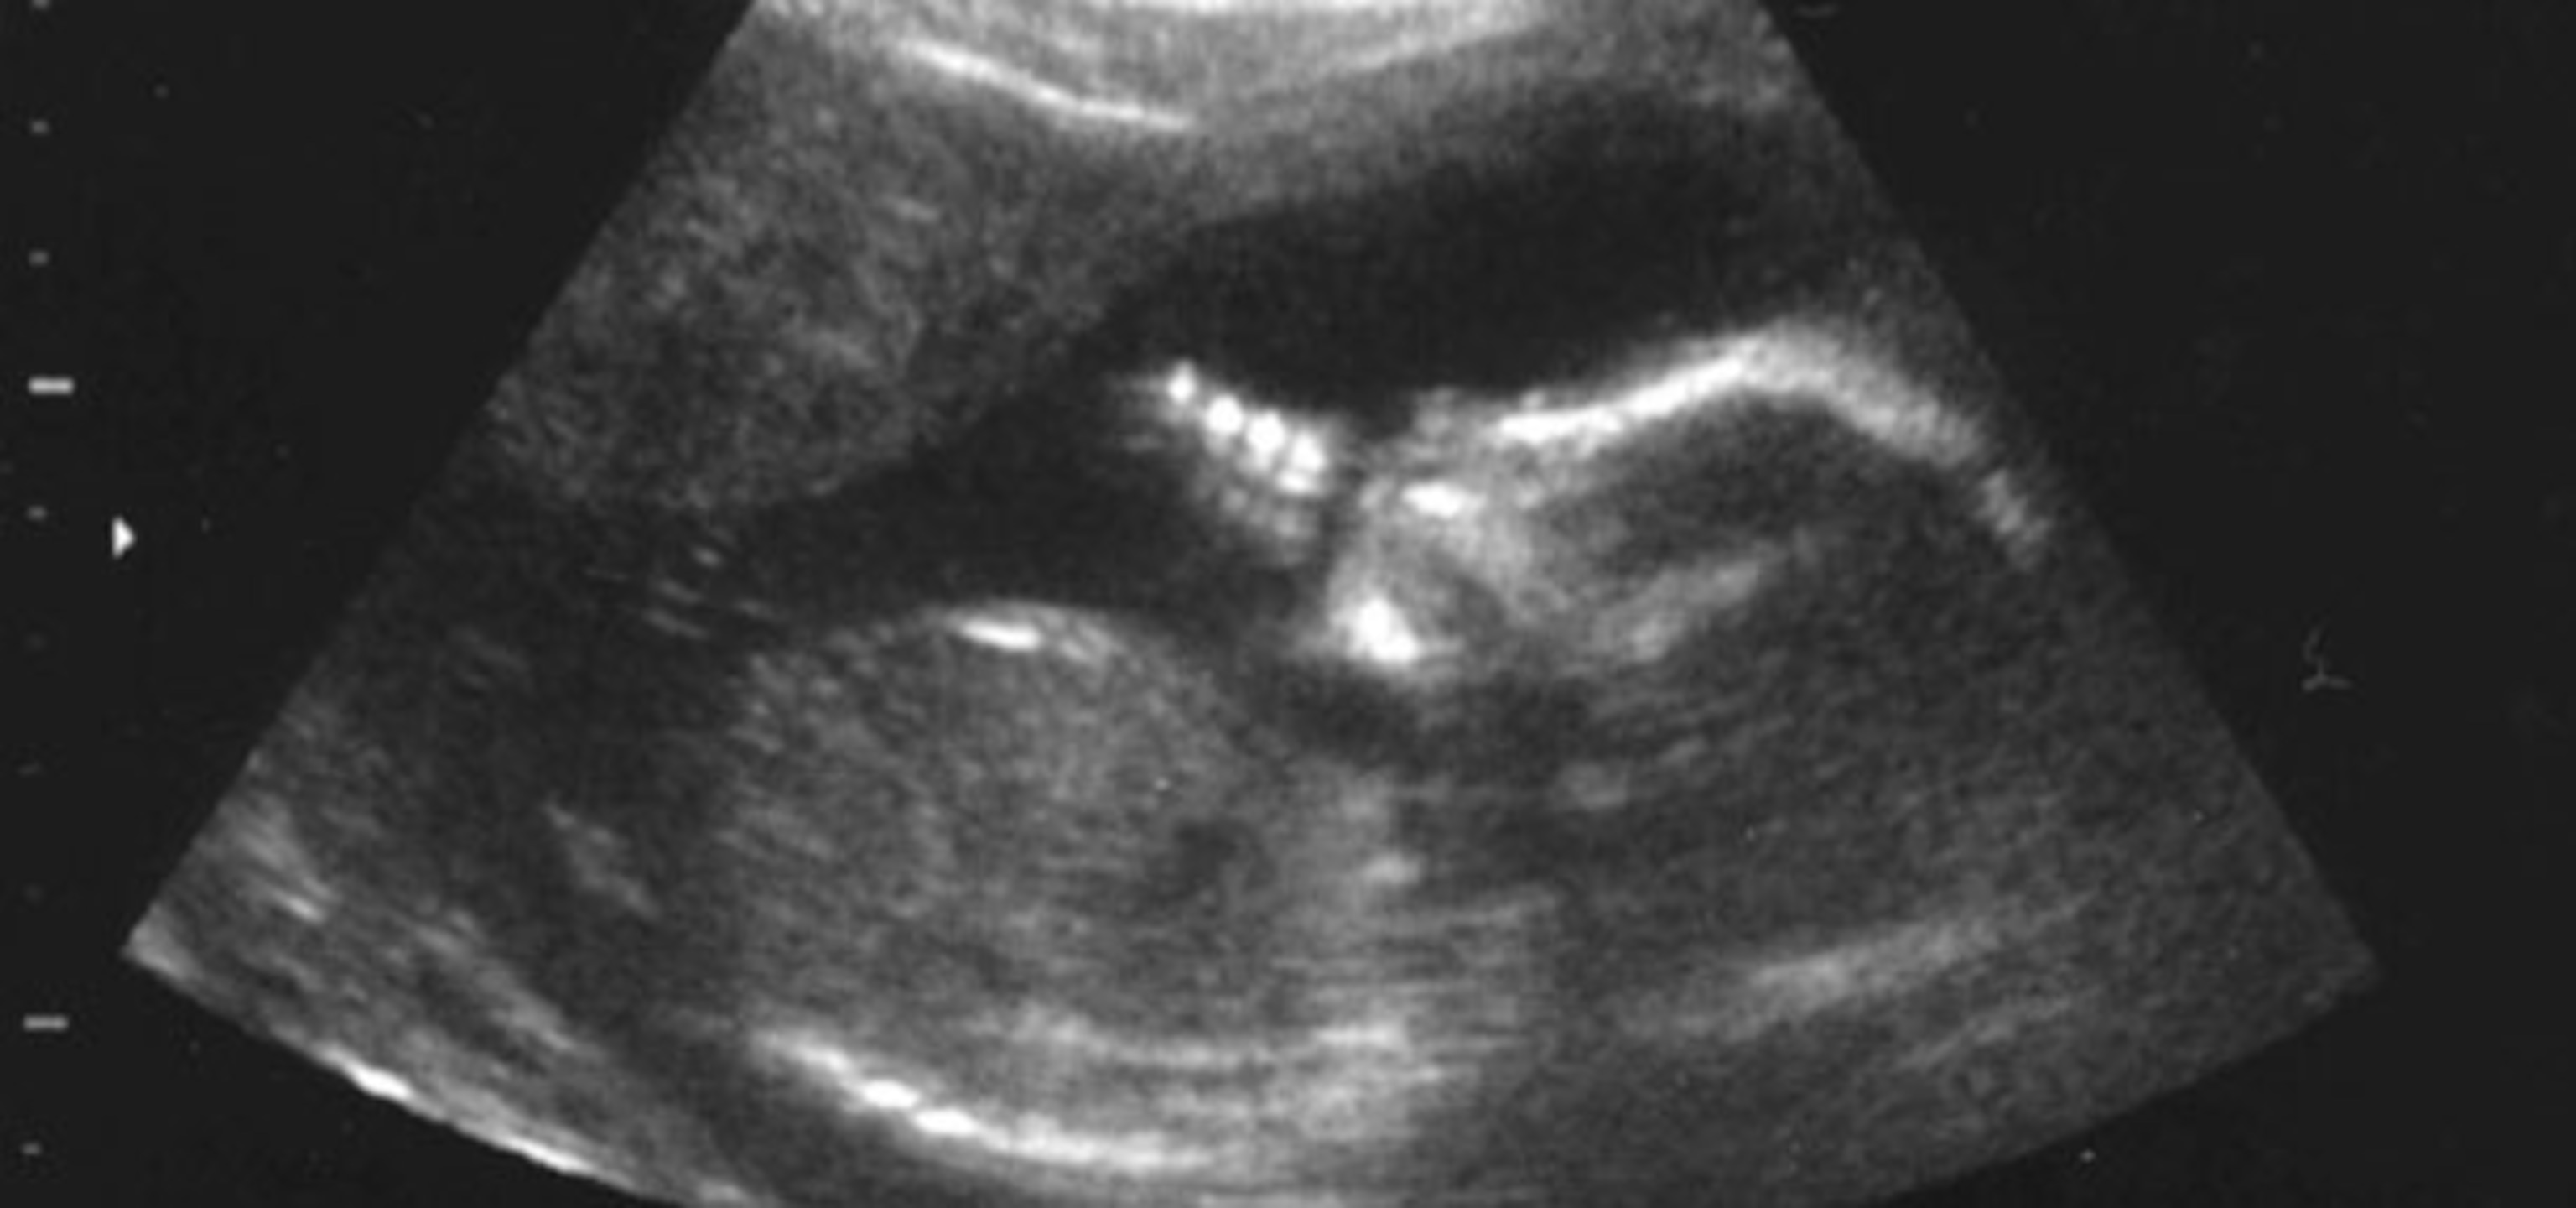

Once a vector is chosen, it must be guided to the right place. For bleeding disorders, it is a relatively simple matter of injecting the vectors into the bloodstream, via the umbilical cord. For diseases that affect more localised organs, ultrasound can help to guide a needle to the right spot.